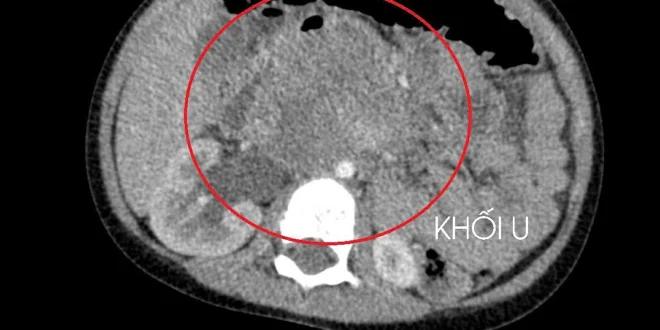

10일 흥붕 종합병원 의사들은 3세 아동이 장기간 복통을 호소했으나, 가족이 외곽 지역에 거주하여 의료 접근이 어려웠다고 전했다. 아동이 병원에 입원했을 때, 종양이 신장을 압박하고 있었으며, 고환암 생검 결과 간과 폐로 전이된 상태로 확인되었다. 이는 아동의 고환이 출생 시부터 음낭이 아닌 복부에 위치하여 명확한 증상 없이 서서히 성장했기 때문이라고 밝혔다.